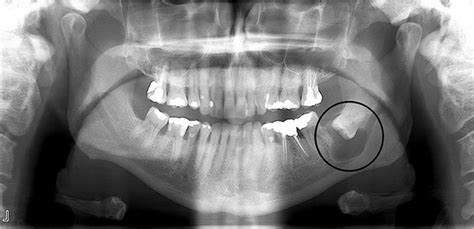

- Quiste dental dentígero: Aparece en torno a la corona dental. Se produce cuando un diente no ha erupcionado al completo, como una muela del juicio.

- Dientes retenidos o en erupción: Cuando un diente (muy comúnmente una muela del juicio) no logra salir correctamente y queda retenido dentro del hueso, se puede formar un quiste dentígero alrededor de su corona. Este tipo de quiste se desarrolla por acumulación de líquido durante el desarrollo del diente.

- Revisión y diagnóstico profesional: Agenda una visita con tu dentista para que evalúe el bulto. El odontólogo examinará la lesión; muchas veces con solo verla y palparla puede identificar de qué se trata. En otros casos solicitará radiografías (por ejemplo, una ortopantomografía) para ver quistes dentro del hueso o asociados a raíces dentales que no son visibles externamente.